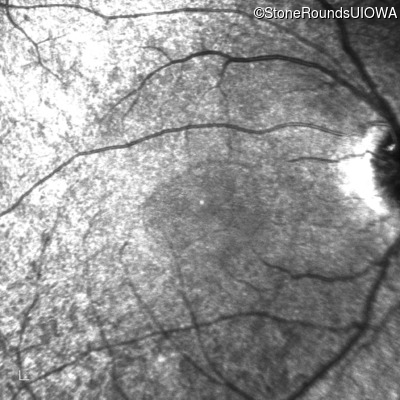

Age at visit: 15 years

This 15 year old male has had very poor vision and nystagmus since the first year of life.

Age at visit: 17 years